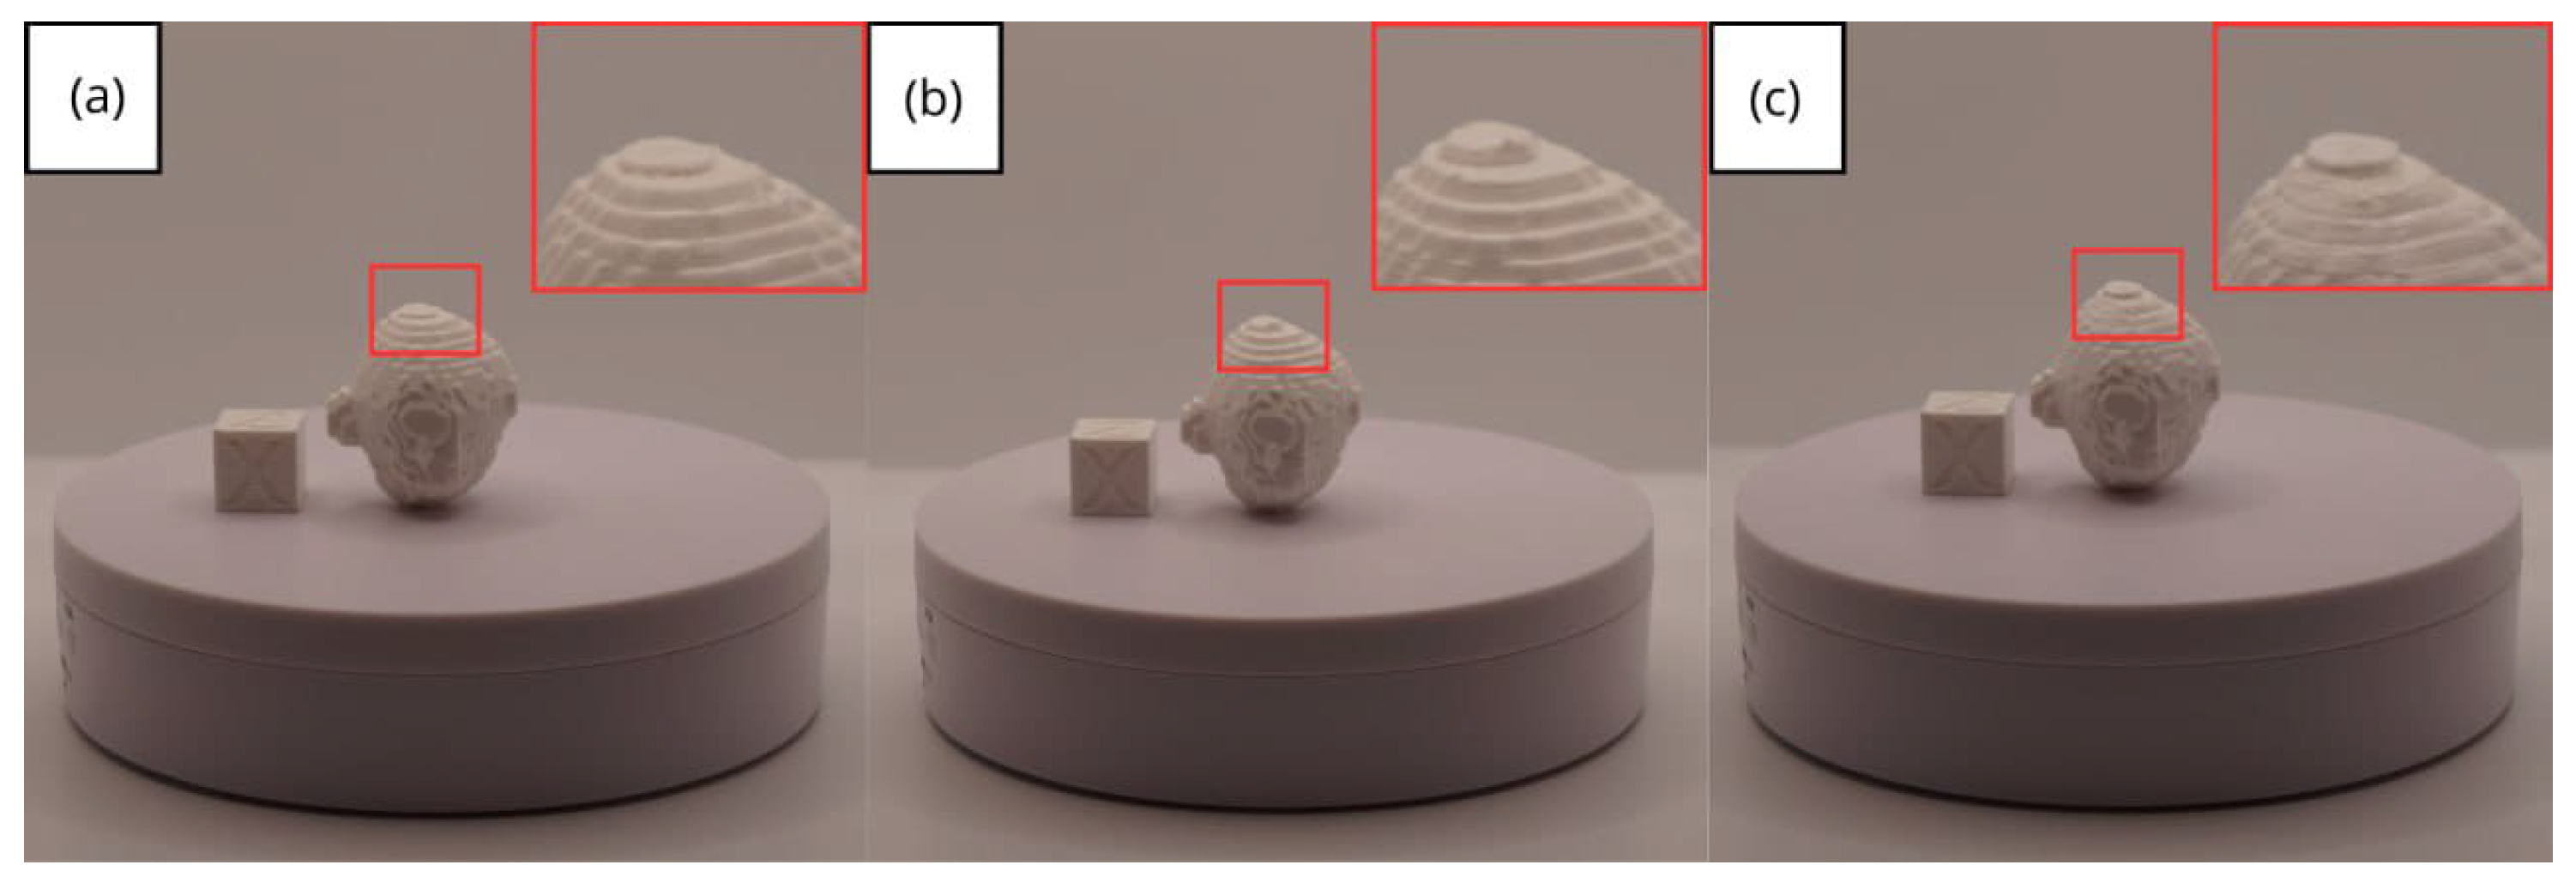

3.3.3. Final Printing

- Resolution loss: We can see in our protocol how the conversion process can lead to a reduction in image resolution, which could affect the fidelity of the 3D models. It is important to consider defining strategies in the DICOM file acquisition process to mitigate this resolution loss problem, such as optimising imaging parameters and carefully selecting segmentation thresholds. These losses are primarily dependent on the imaging process and are, therefore, beyond our control and the development of this protocol.

- Segmentation errors: The potential for inaccuracies to occur during the segmentation phase is acknowledged, with emphasis placed on the difficulties in distinguishing between tissues of similar densities. We emphasise the importance of operator experience and the use of advanced segmentation tools to minimise these errors.